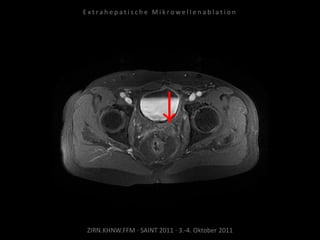

Verlaufskontrolle:

MRT 12.10.2010

Restvitalität dorsal der Harnblase.

Erneute Ablation am 04.11.2010:

2 Nadelpositionen.

CTs und MRTs

CT vom 08.02.2011

Kein Vitalitätsnachweis.

Resultat:

Erfolgreiche Behandlung des

Tumorrezidivs.

Fazit:

Die MWA ist geeignet, um Tumorgewebe

an kritischer anatomischer Position zu

behandeln.